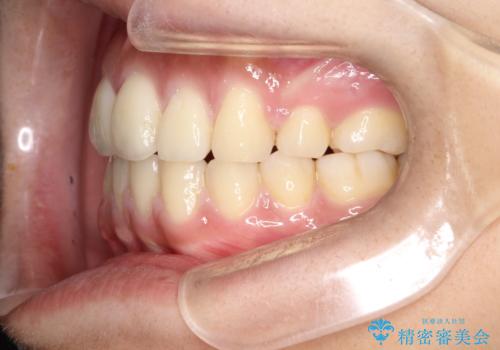

横顔をすっきりさせたい 下の前歯が1本少ない方の変則的な抜歯矯正

口元の突出感がありと、下顎の前歯が1本欠損していました。

上顎の前から両側の前から4番目の歯と、下あごの前歯を1本抜歯して、口元をすっきりさせる計画としました。